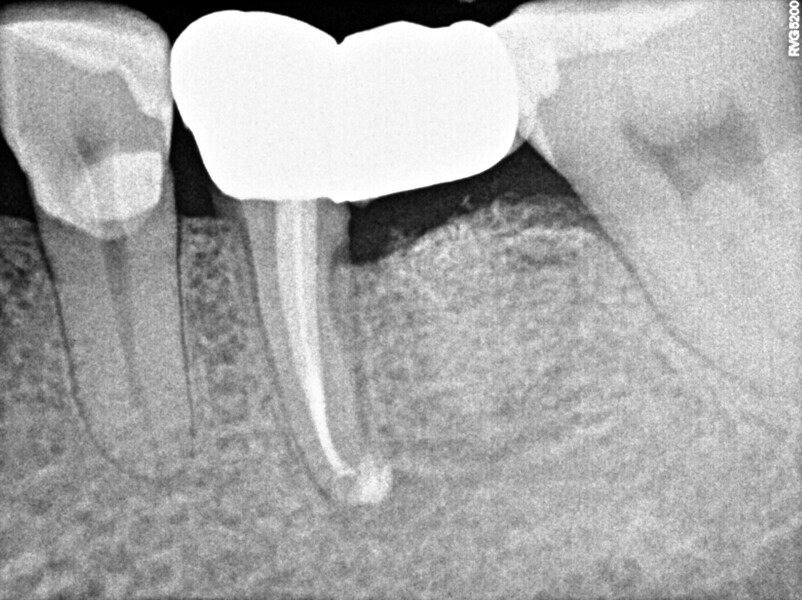

A 50-year-old patient with non-contributory systemic disease presented with the main complaint of pain on mastication. He reported having had a direct restoration on the mandibular left first molar six months earlier. On clinical and radiographic examination, a large, overextended amalgam Class II filling was observed as well as a J-shaped radiolucency on the distal aspect of the tooth (Fig. 1). A buccal swelling oriented distally was also present, as were characteristics of occlusal wear compatible with bruxism on the patient’s dentition. The tooth had pain on percussion and responded negatively to electrical and thermal stimulus tests. When probing in the region of the abscess, a 9 mm isolated pocket was identified (Fig. 2). The tooth was diagnosed with pulpal necrosis and periapical abscess and a suspected VRF. To confirm the presumptive diagnosis, an access cavity was prepared under dental dam isolation and under the dental operating microscope. When the previous restoration was removed, a longitudinal fissure line was detected on the distal aspect of the pulpal floor at higher magnification (10×).

Upon this finding, the hemisection procedure was discussed with the patient, and he gave his full consent to perform it. Initially, the distal canal was gently irrigated with sodium hypochlorite at a 5% concentration and the canal medicated with calcium hydroxide (Fig. 3). At a second appointment 15 days later, the buccal abscess had receded (Fig. 4). The mesial root canal was then treated conventionally, determining the working length with an electronic apex locator (Root ZX II; Morita), performing instrumentation with nickel–titanium files (Pro-Flexi Files, Denco) and obturating with gutta-percha and a bioceramic sealer using the single-cone technique (CeraSeal, Meta Biomed). A resin core was placed with a dual-polymerising composite (CompCore AF, Premier Dental; Figs. 5 & 6).

One year later, the restoration was performing well and the patient was asymptomatic. Radiographs and a CBCT control scan showed complete bone healing. On the periapical radiograph, the tooth showed a healthy periodontal ligament and no signs of failure in the restoration (Fig. 12). The cross-sectional, axial and coronal views of the CBCT scan showed good bone width and height and no pathological findings (Figs. 13–16). The oclusal scans and clinical images showed good adaptation of the new restoration and a healthy gingiva (Figs. 17–20).